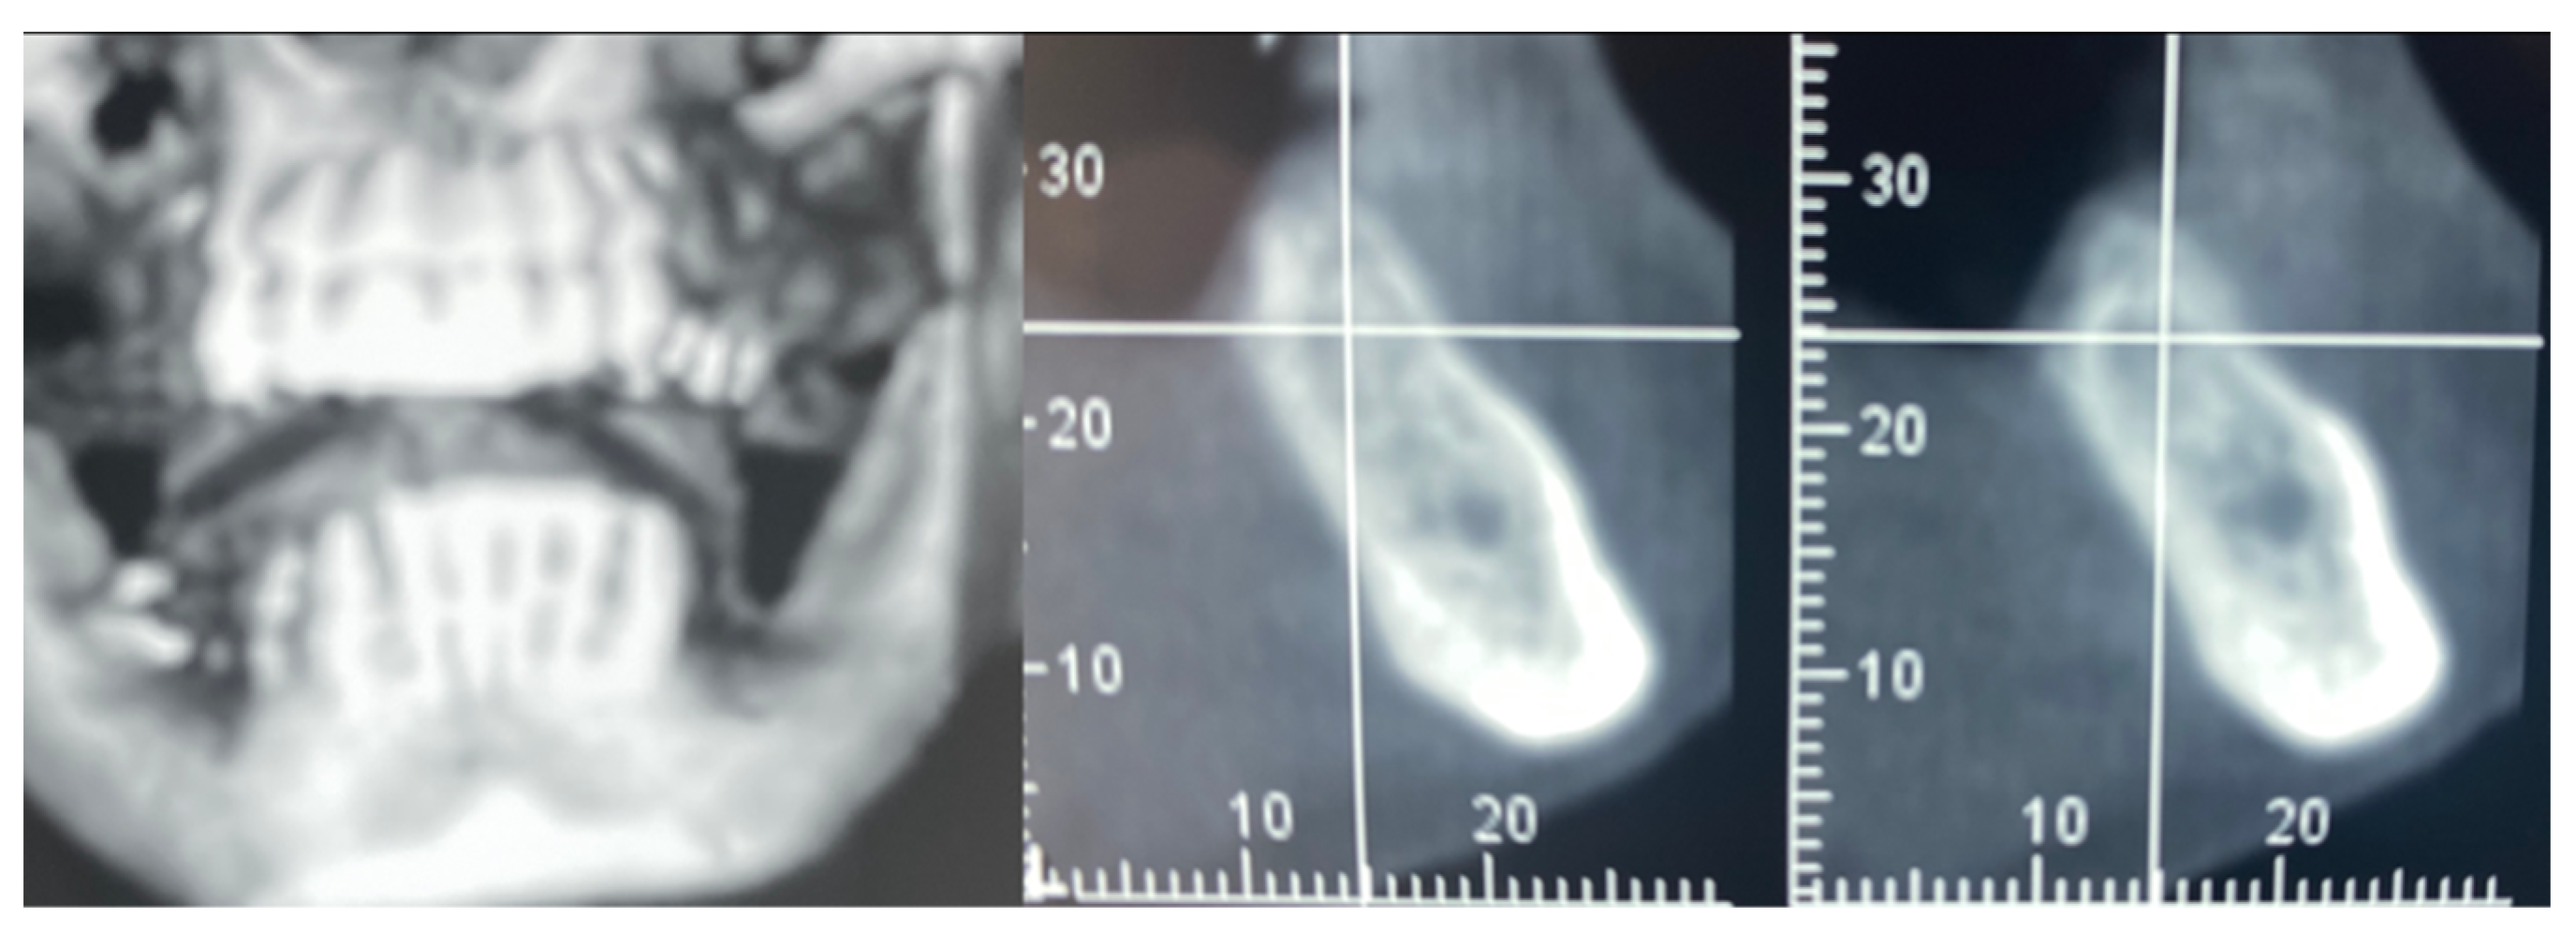

Figure 3.

CBCT at baseline: (a) volumetric reconstruction of the edentulous area; (b) cross-section of the area.

A 61-year-old female patient came to our attention. The clinical evaluation revealed a severe atrophic ridge in the left posterior mandible (Figure 2a). The patient stated that the teeth were extracted 5 years before and the first bicuspid only a month before the consultation. The radiographic evaluation showed the presence of a residual root fragment (Figure 2b). It was also possible to observe the radiolucency of the healing socket of the first bicuspid. The patient was further evaluated with a CBCT to complete the case documentation and data collection. The CBCT showed a severely atrophic ridge with an unfavorable anatomy for dental implant insertion (Figure 3).

In this case of important bone augmentation, a healing period of 8 months was observed. Indeed, biomaterials, such as FCS, require a longer time than autogenous bone. No complications were experienced during the follow-up. At the end of the healing period, CBCT was performed to plan the implants’ insertion (Figure 8). It was pleasant to observe that the GBR provided the desired volume augmentation for the ridge. The CBCT showed a horizontal and vertical ridge augmentation of 8 mm and 8 mm, respectively.

Figure 8.